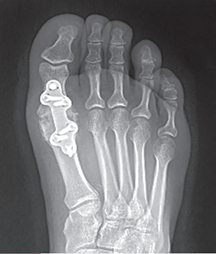

Arthrodesis With a Plate and Screws

Arthrodesis using a plate and screws.

Reproduced from Orthopaedic Knowledge Update 5: Foot and Ankle, p. 198.